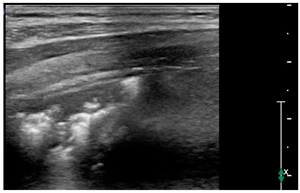

- Broken pleural line with subpleural consolidations < 1 cm

![]() | PATTERN 4 Broken pleural line with subpleural consolidations <1 cm |